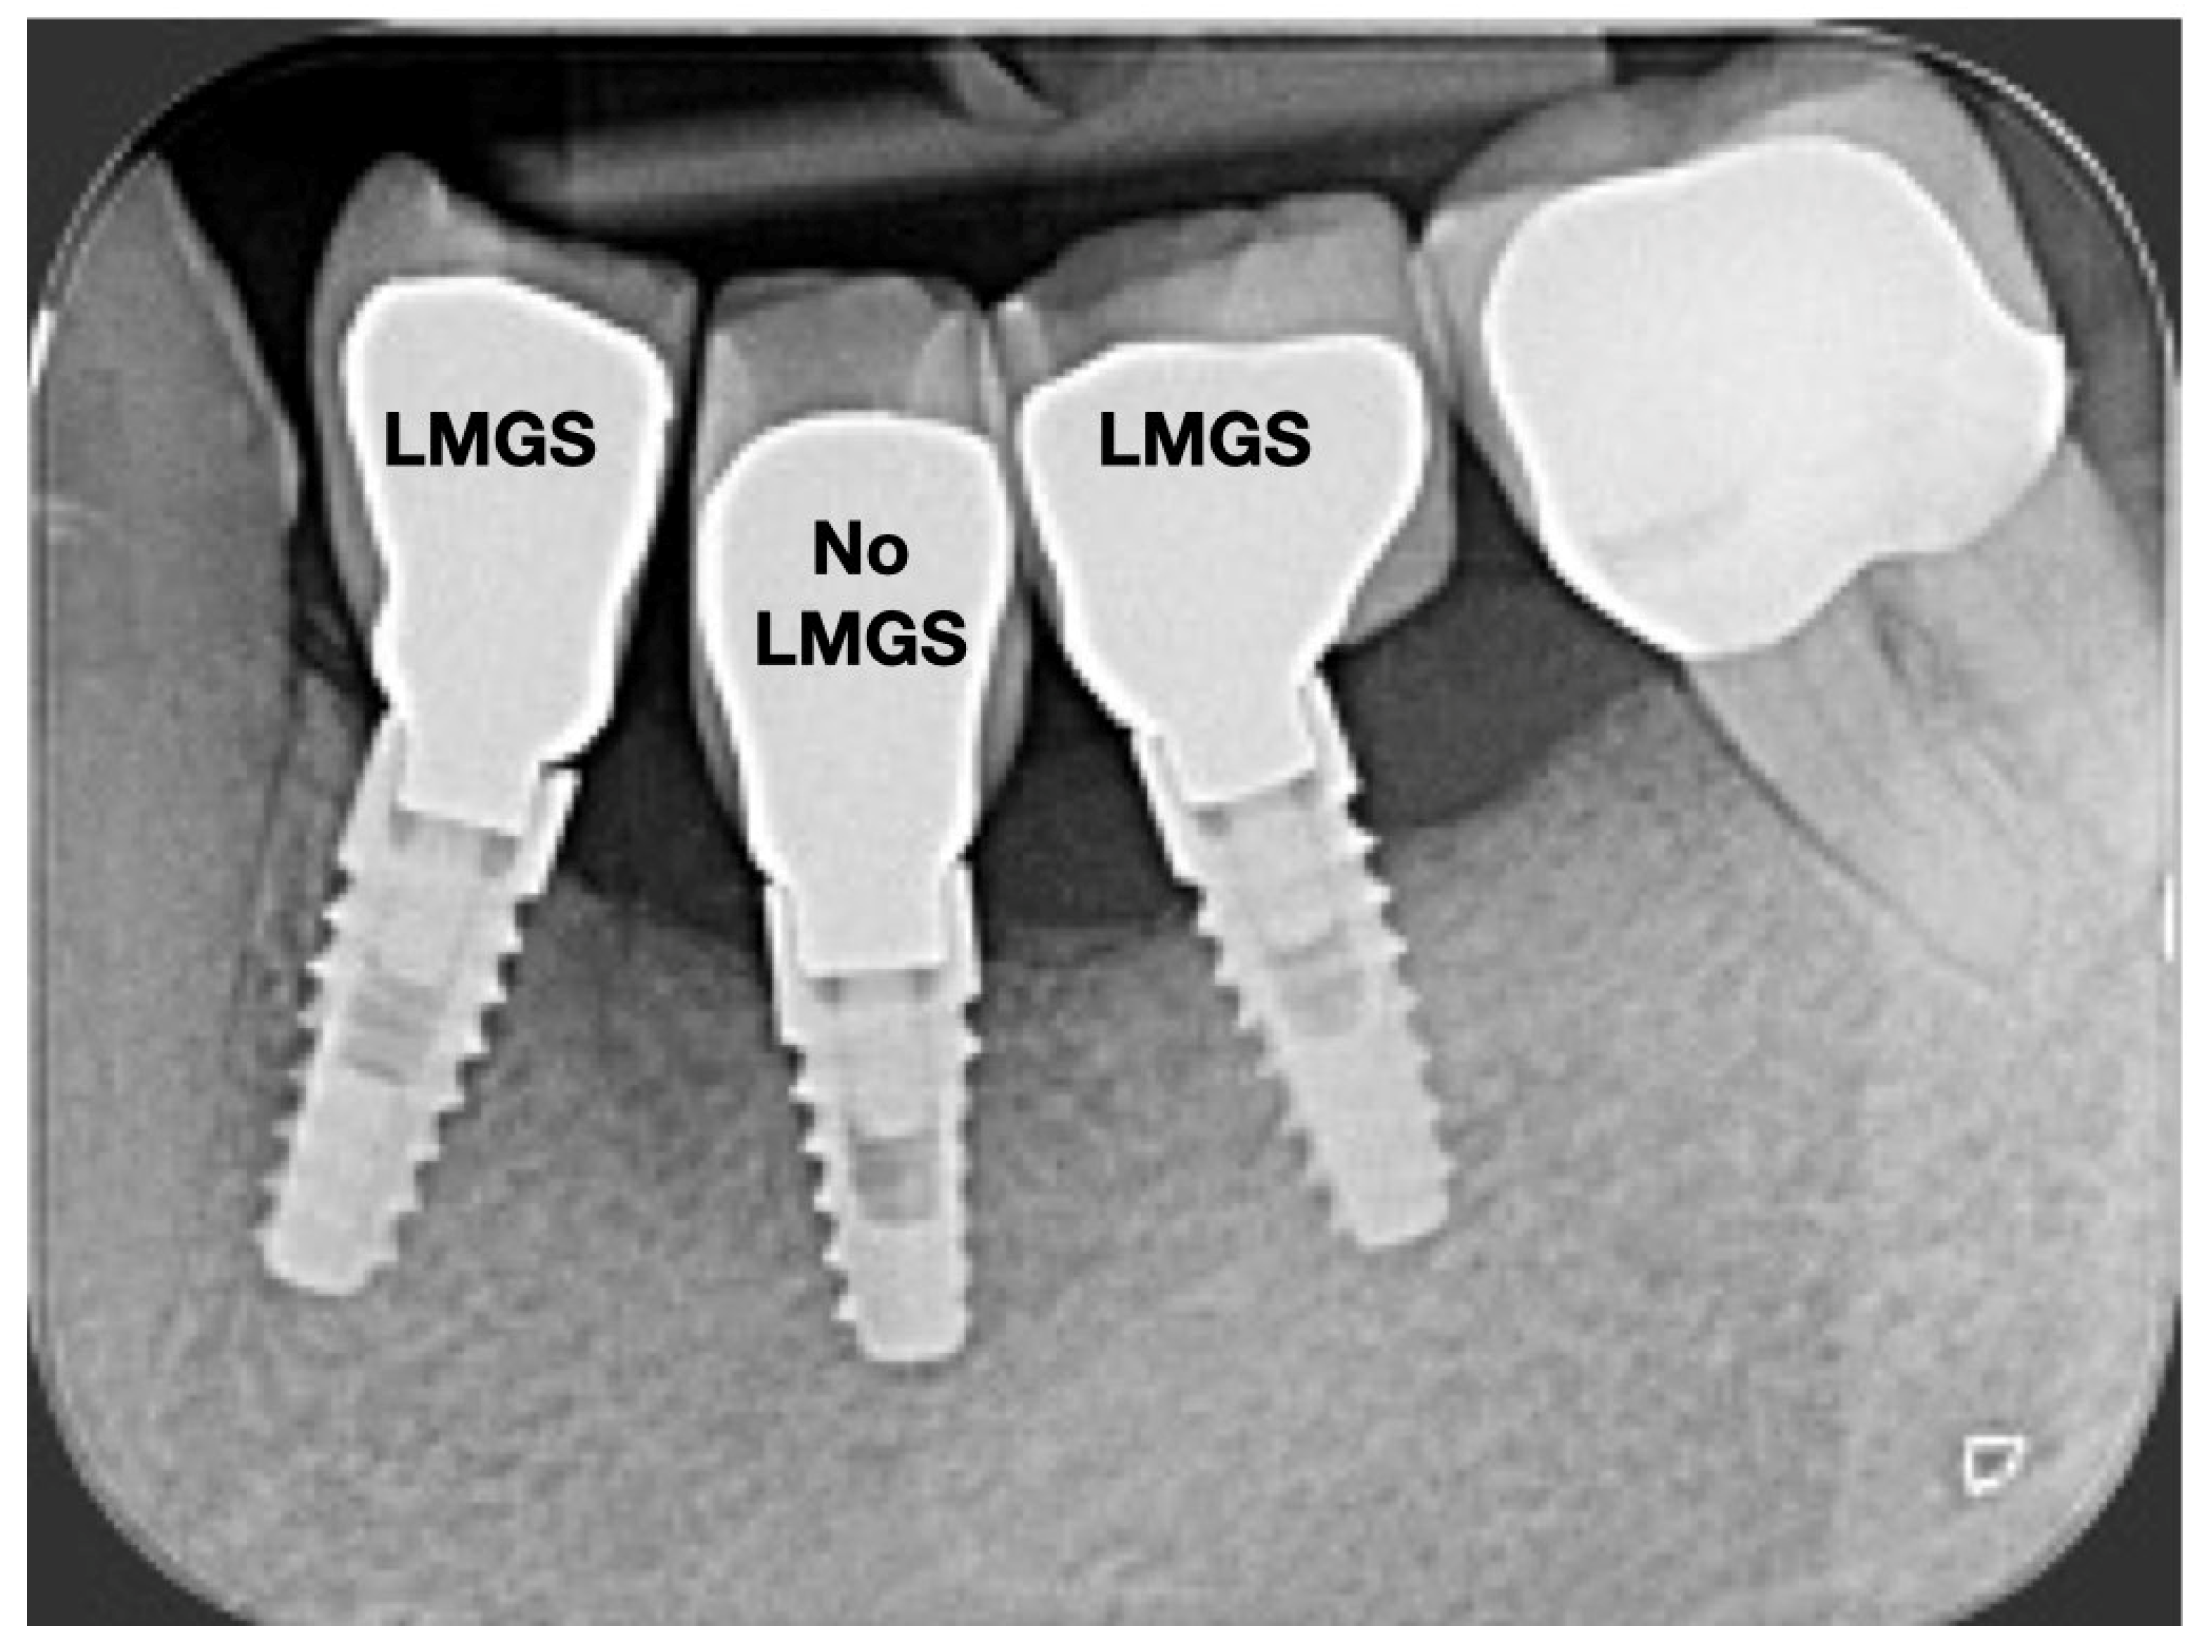

A total of 164 LMGS implants (37.4%) and 195 no-LMGS implants (42.1%) presented PIM. Differences between LMGS implants and no-LMGS implants were not statistically significant (p > 0.05). A total of 28 (6.3%) LMGS implants and 98 (21.1%) no-LMGS implants demonstrated P with a statistically significant difference (p < 0.01). Figure 2, Figure 3, Figure 4 and Figure 5 report examples of radiographs during follow-up.

Figure 5.

Radiograph of the same three (3) implants at the 15-year follow-up. Signs of P can be noted around the No-LMCS implant. (LMGS = with a laser-microgrooved collar surface; No-LMGS = without a laser-microgrooved collar surface).